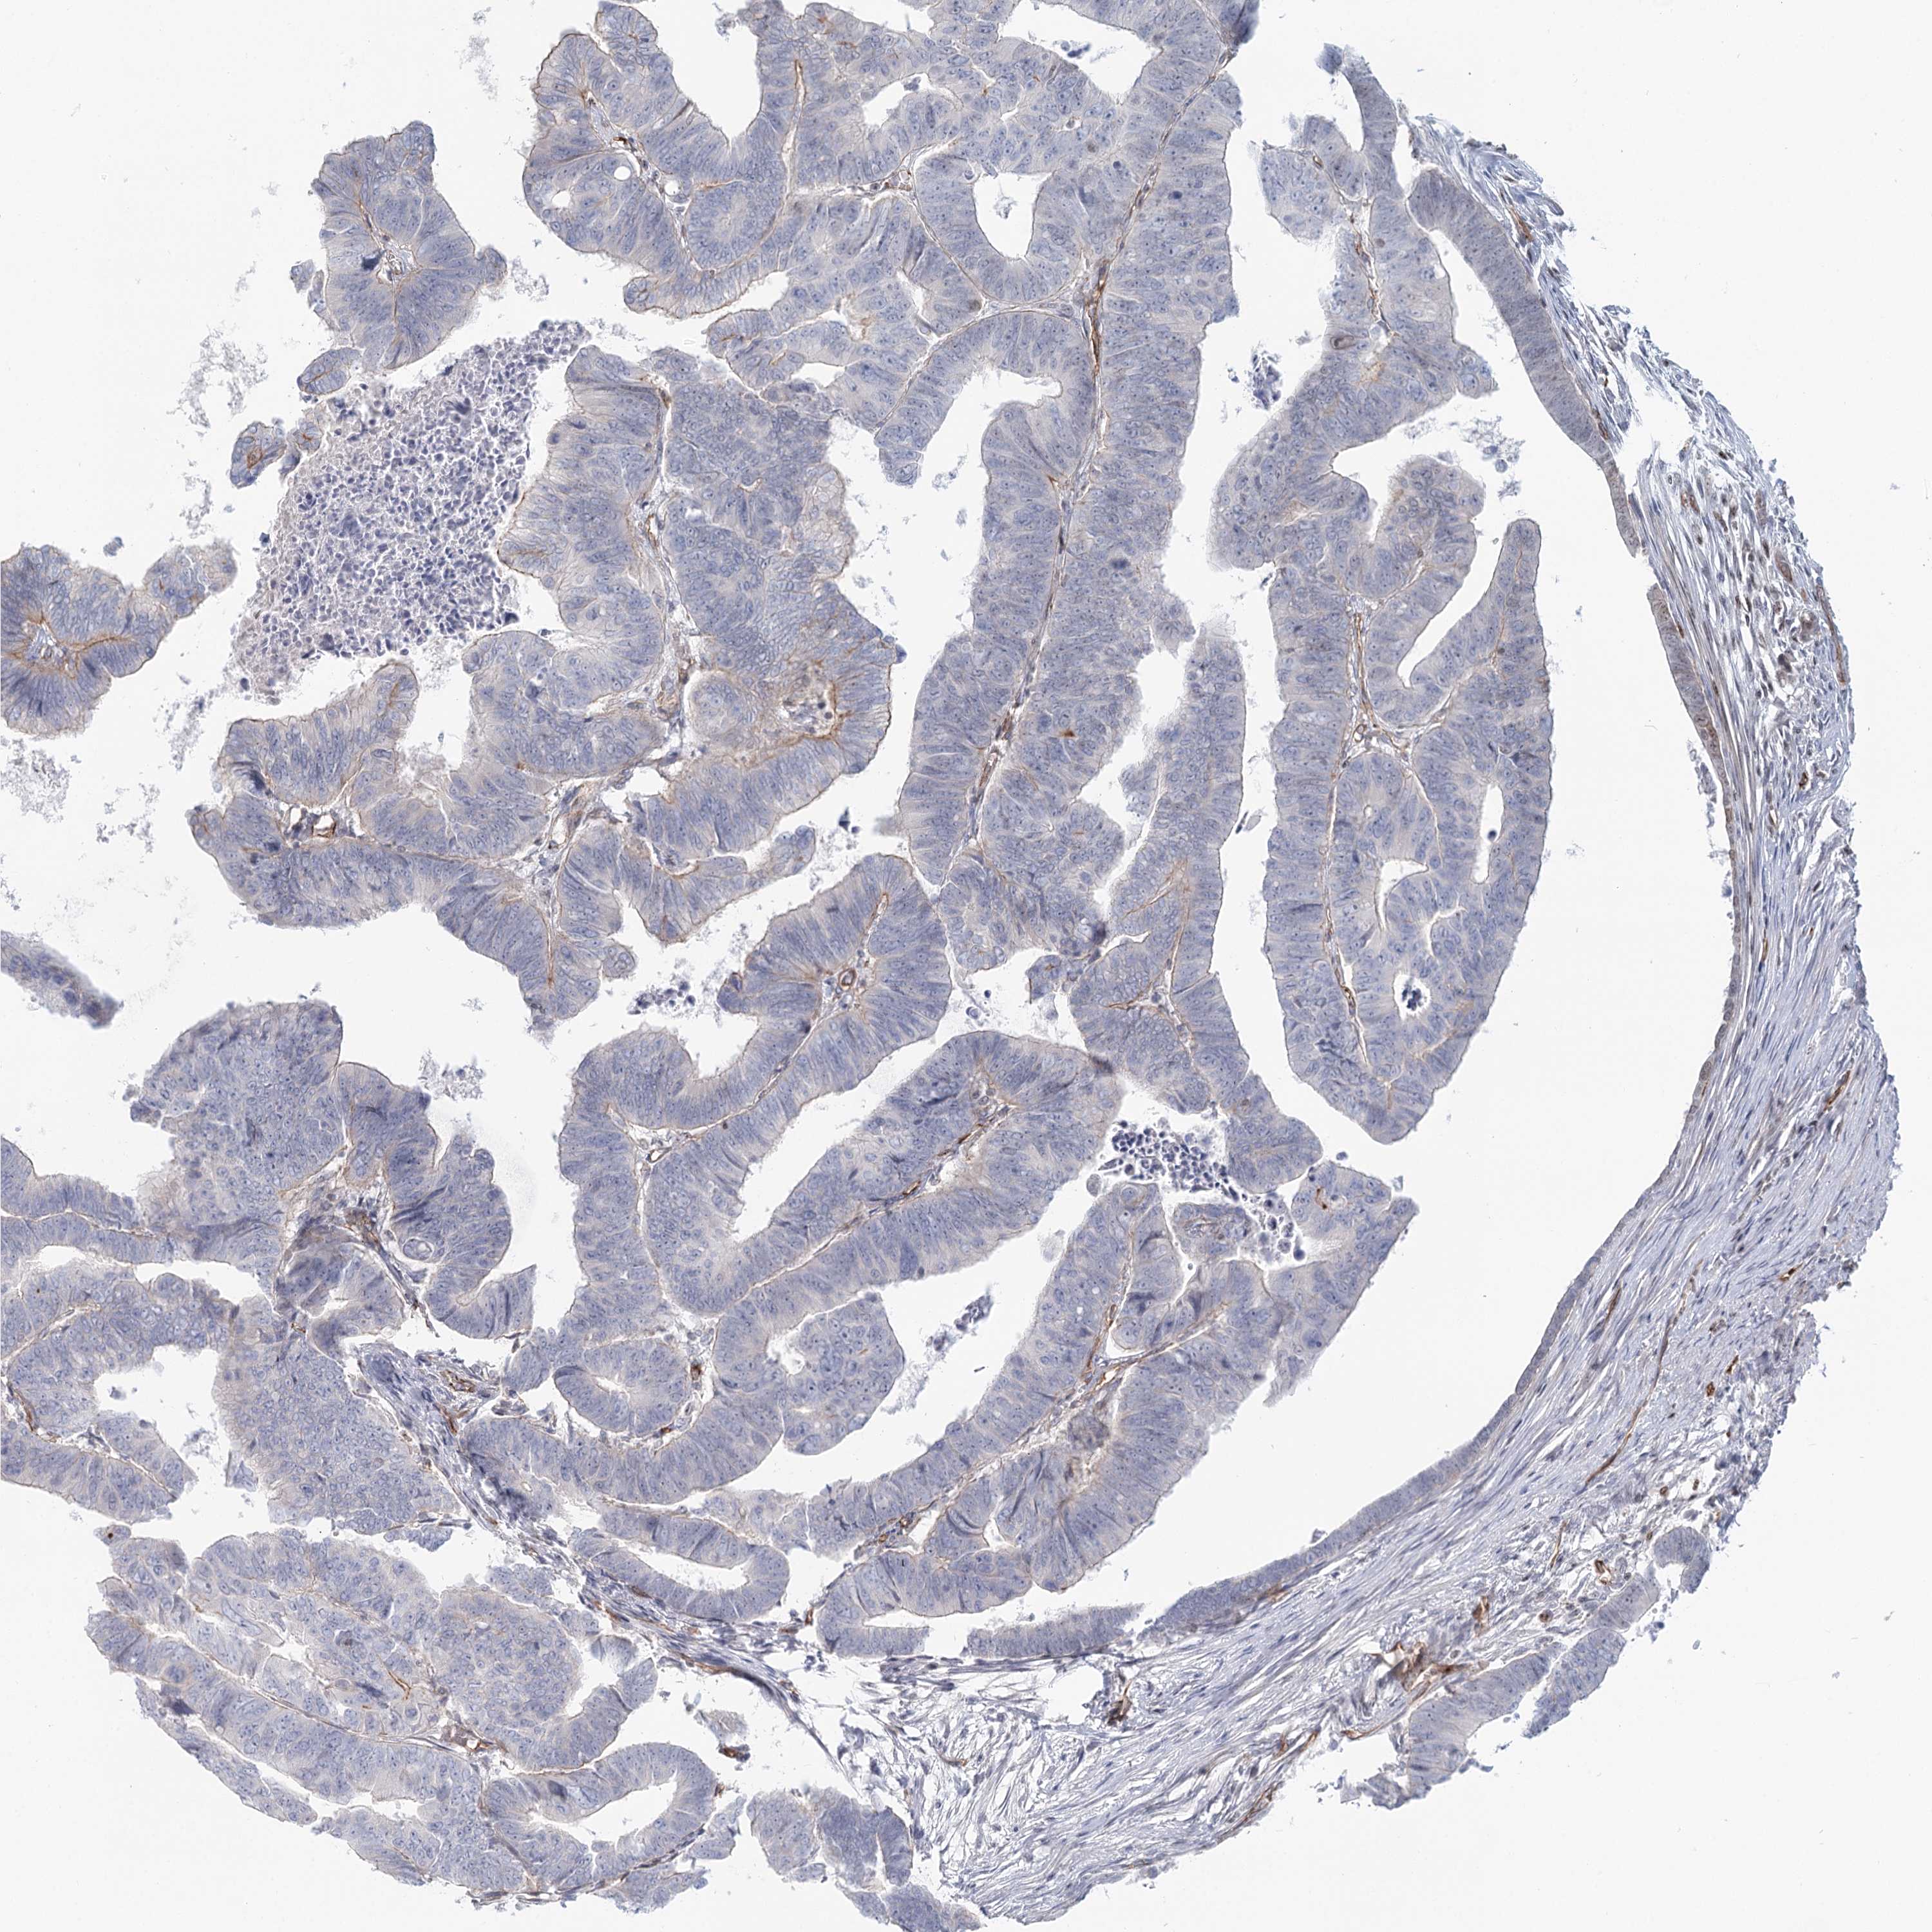

CANCER COLORECTAL CANCER Show tissue menu

ANTIBODIES

AND

VALIDATION